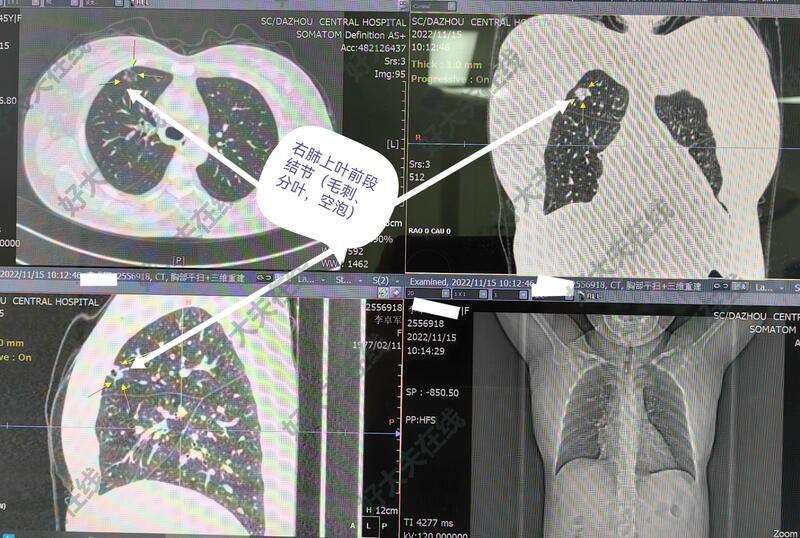

图1-5,女性,45岁,体检发现右肺上叶前段结节,亚实性(磨玻璃)结节、毛刺、分叶、胸膜牵拉等,短期随访结节不消散。胸腔镜微创手术切除,病理报告为肺浸润性腺癌。